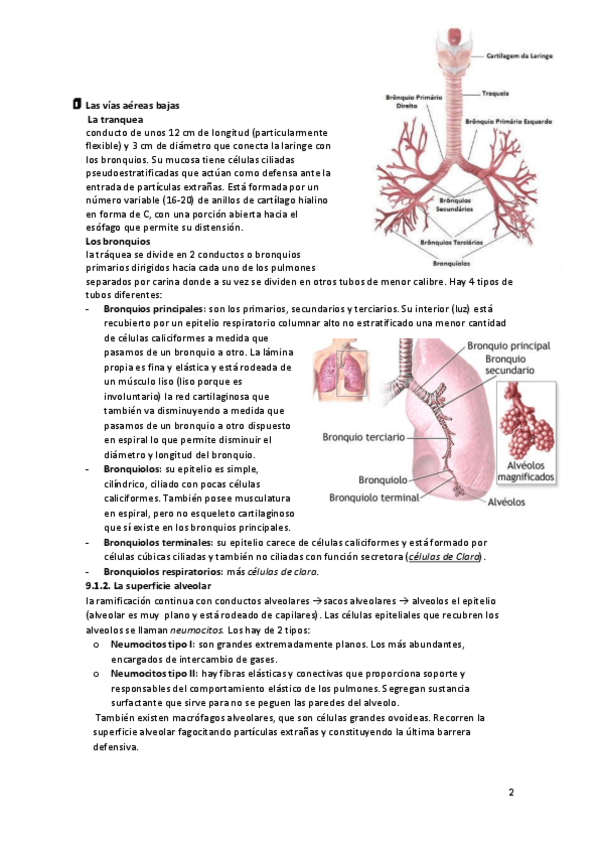

He publicado nuevos apuntes de Fisiopatología general: tema-9-aparato-respiratorio.pdf